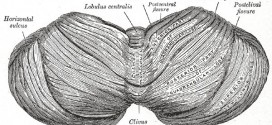

La adiadococinesia. Dificultad o incapacidad para controlar o efectuar ciertos movimientos musculares, especialmente a la hora de detener un impulso y sustituirlo por otro opuesto. Puede observarse en trastornos neurológicos del cerebelo. La adiadococinesia es, la incapacidad para realizar con rapidez movimientos alternantes sucesivos por ejemplo, la pronación y la supinación de la mano. Es una exploración fácil y una …